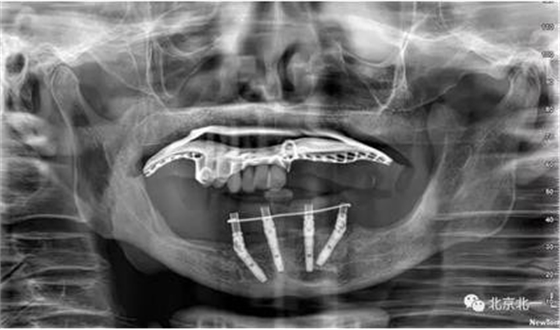

術(shù)前檢查片下頜骨季度萎縮,右側(cè)下頜下牙槽神經(jīng)管幾乎位于牙槽嵴頂。不能行常規(guī)種植。采用A04技術(shù)可實(shí)現(xiàn)即即刻種植一日戴牙夢(mèng)想。

圖一至圖六明顯看出右側(cè)頦孔位于牙槽嵴頂。很清晰看出頦孔區(qū)的U型形狀。

圖七:采用A04技術(shù),拔除下頜余留牙,修整骨平面。在頦孔前方傾斜植入兩枚植體,避開(kāi)頦孔。減少懸臂。前牙區(qū)植入兩枚直的植體。完成即刻修復(fù)。一日得牙,缺牙后多少年來(lái)都沒(méi)有吃過(guò)蘋(píng)果的滋味,到種植牙時(shí)代,想吃什么就吃什么, 我的健康我做主。